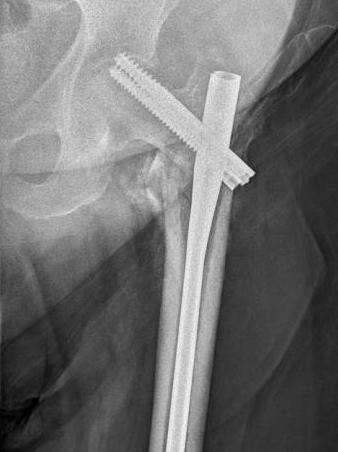

Sliding hip screw/dynamic hip screw

Dynamic hip screw

Mechanism

Plate is a lateral tension band whilst the sliding screw allows controlled fracture impaction

Technique

Guide wire

- centred in femoral head in 2 planes

- tip-apex distance < 25 mm

Tip - apex distance

- from tip of screw to apex femoral head

- accumulative on AP and lateral

- > 25 mm, increases cut out